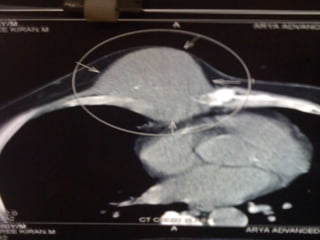

• USG ABDOMEN- HETEROECHOIC LESION

RIGHT LOBE OF LIVER-11.5×10.5 CM –

• IMPRESSION- HCC Rt. LOBE OF LIVER

INVESTIGATIONS • CBC- NORMAL •LFT- S. BILIRUBIN- 1.3 DIRECT- 0.9 ALK.POS- 80 T.PROT- 6.8 ALB- 3.7 • RFT- NORMAL • HbSAG- NEGATIVE • ANTI HCV- NEGATIVE • HIV I & II- NEGATIVE • ALPHA-FETO PROTEIN- 1.62 IU/ml • USG ABDOMEN- HETEROECHOIC LESION RIGHT LOBE OF LIVER-11.5×10.5 CM – • IMPRESSION- HCC Rt. LOBE OF LIVER